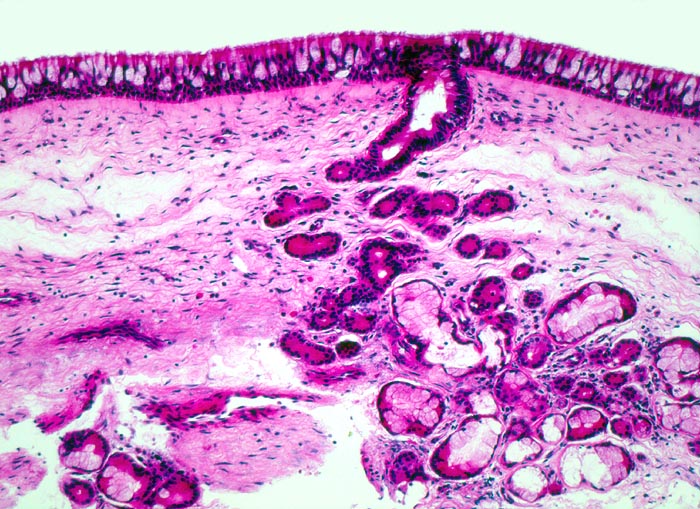

Morphologische Merkmale:

• Polypoides Gewebsfragment bedeckt von mehrreihigem Flimmerepithel.

• Herdförmige Schleimhauterosionen.

• Ödematöses Stroma mit gemischtem Entzündungsinfiltrat: Lymphozyten, Plasmazellen, Histiozyten und zahlreiche eosinophile Granulozyten.

• Im Zentrum des Polypen Drüsenläppchen und zahlreiche Blutgefässe.